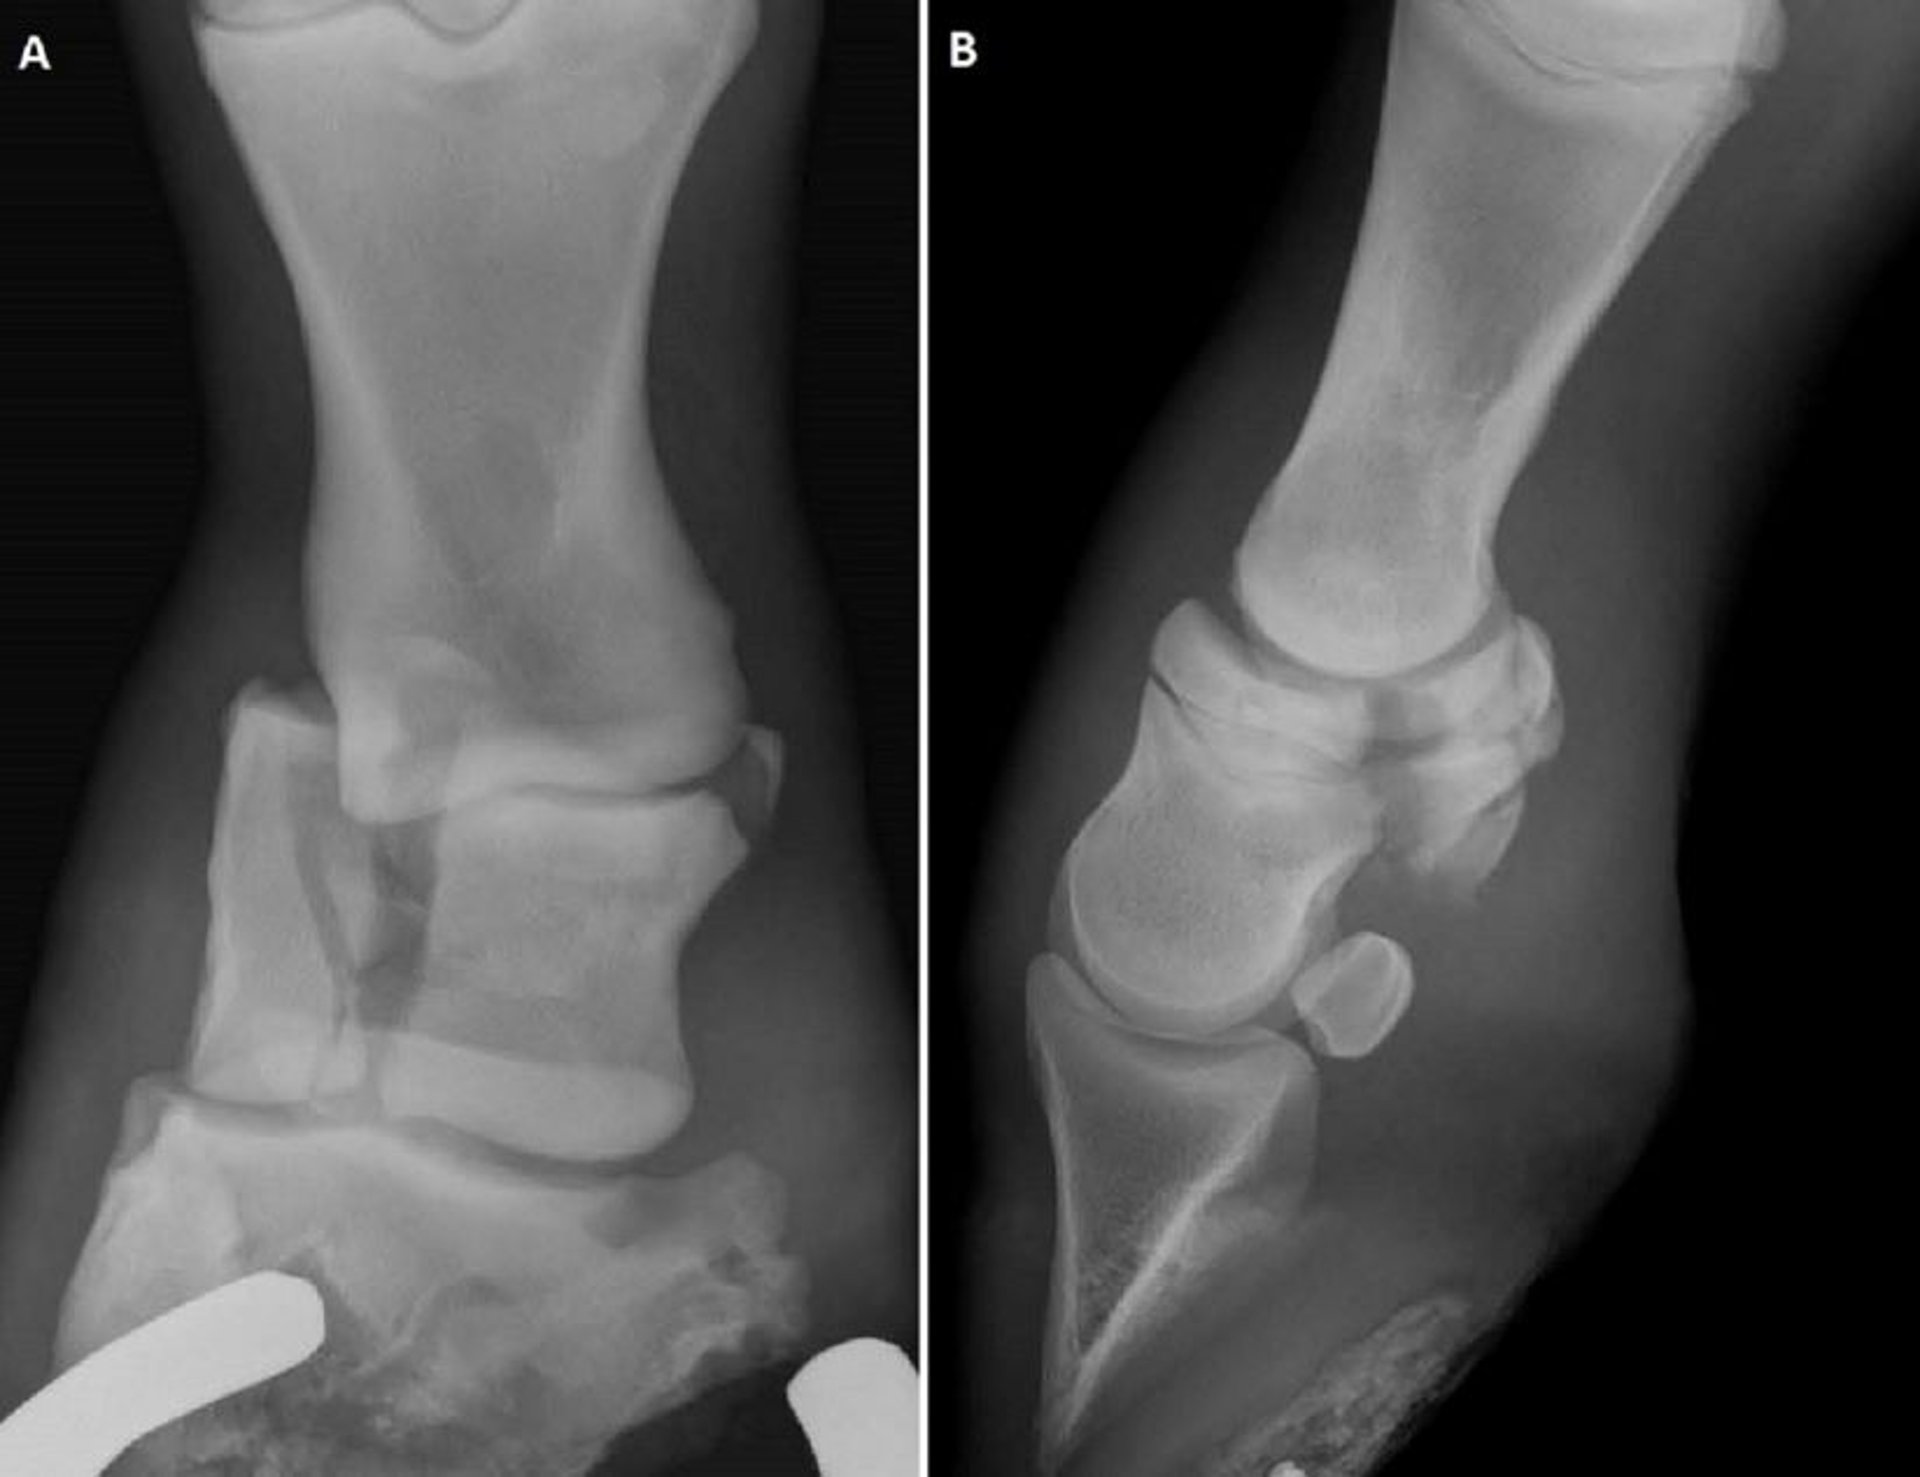

Imágenes radiográficas que muestran diferentes configuraciones de fracturas de la segunda falange en caballos. (A) Radiografía dorsopalmar de una fractura conminuta de la P2. (B) Radiografía lateromedial que muestra fracturas biaxiales de la eminencia de la P2 en un potrillo.

Cortesía del Dr. Matthew T. Brokken.